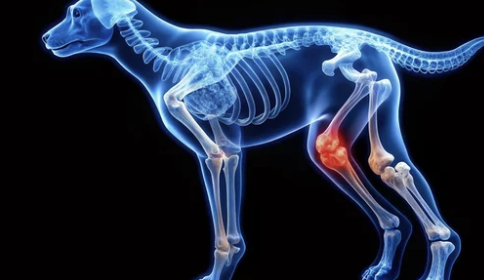

1. 슬개골탈구란?

슬개골탈구는 무릎 뼈(슬개골)가 정상 위치에서 벗어나 바깥쪽이나 안쪽으로 밀려나는 질환입니다.